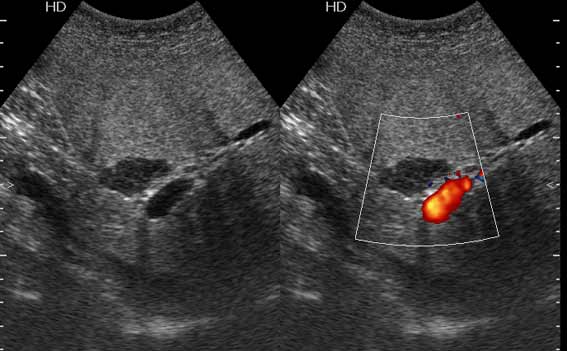

В печени выявлен гипоэхогенный очаг неокруглой формы, аваскулярный при цветовой доплерографии.

Сонограммы, КТ- артериальная, портальная и отсроченная паренхиматозная фазы

Простая и одновременно "сложная" задачка. По УЗИ; явный стеатоз печёночной паренхимы (теперь ключевые слова); на ФОНЕ СТЕАТОЗА определяется гипоэхогенное образование. Варианты? Очаговое образование; и менее вероятно участок гипостеатоза (но не похоже, есть чёткие границе, + не та локализация).

Вывод: надо иметь ввиду, что эхогенность это относительное понятие, эхогенность гемангиомы может изменятся при изменении положения обследуемого пациента (см. прикреплённую статью); не надо забывать что эхогенность образование это понятие относительное, т.е. относительно окружающей паренхимы печени! При стеатозе, гемангиома может выглядеть гипоэхогенно по отношению к гиперэхогенной паренхиме окружающей печени. И главное, есть сомнение-заказываем таргетное мультифазовое КТ.